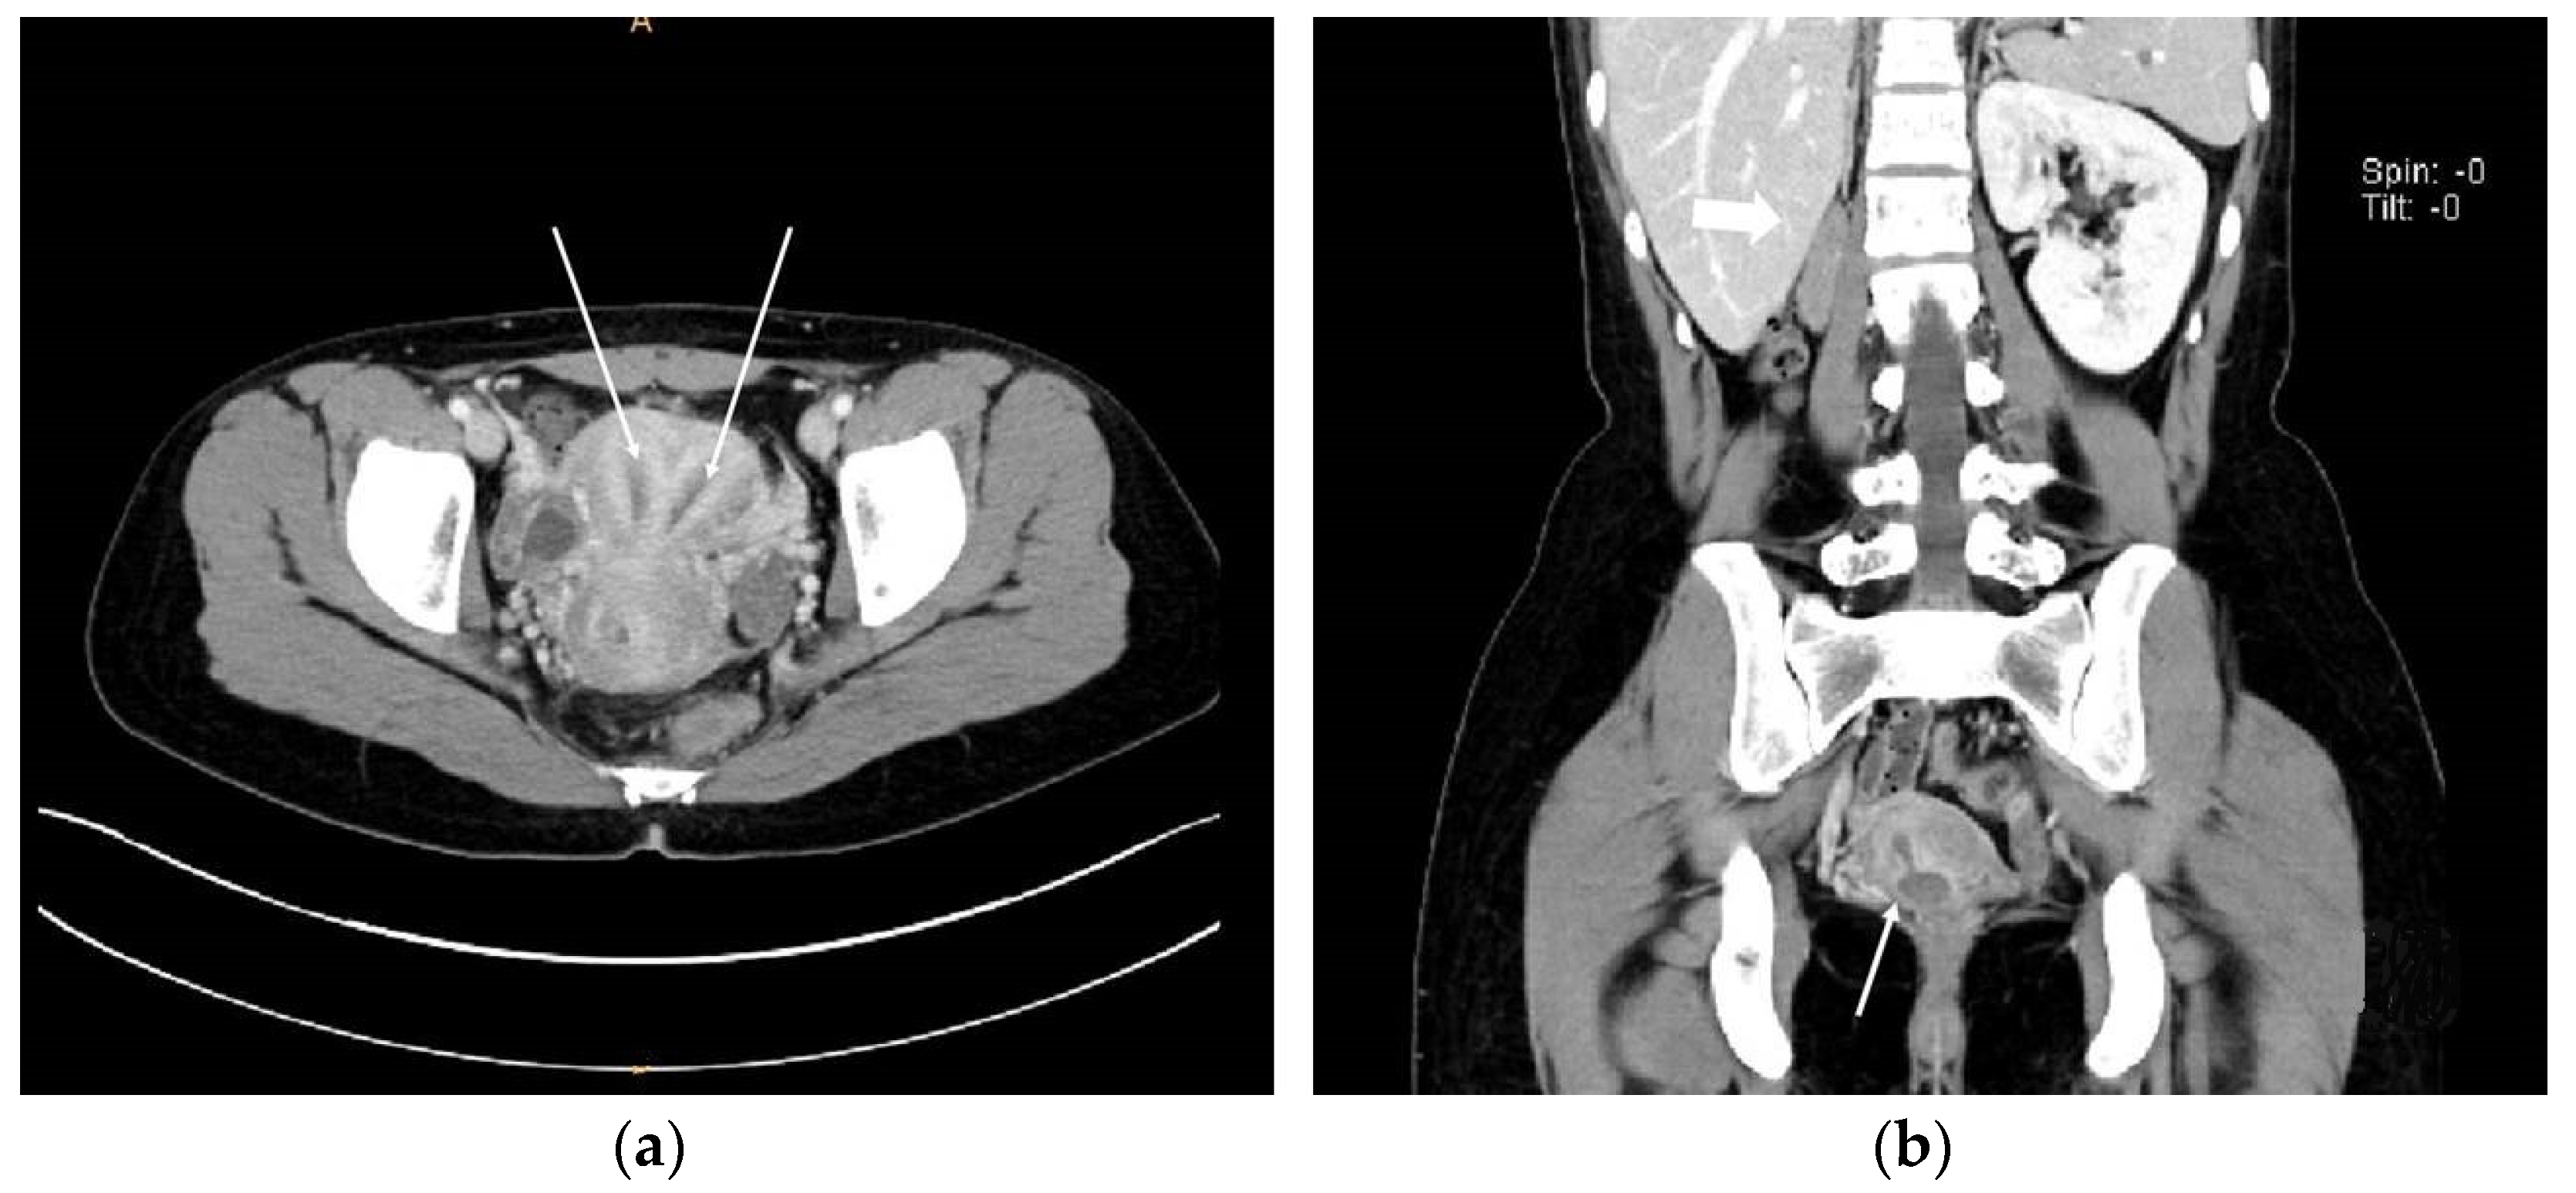

On the abdominopelvic CT image taken at the ER, we noticed she had HWW syndrome (right side hemi-vagina and right kidney agenesis) with acute pyelonephritis (APN) of the left kkidne (Figure 3a,b). After admission, transvaginal USG (Figure 4) and pelvic MRI (Figure 5a–c) were performed. We planned to perform the vaginal wall resection surgery on the next menstrual period as she needed antibiotics treatment for the APN, and the amount of hematocolpos was not so extensive that we could not clearly identify the bulging vaginal wall.

Figure 3.

Abdominopelvic CT images. (a) Axial view showing the two uterine corpuses (indicated with white arrows); (b) Coronal view suggesting Herlyn-Werner-Wunderlich syndrome. White thick arrow; agenesis of right kidney. White thin arrow; hematocolpos of obstructed hemi-vagina connected with right endometrial cavity.